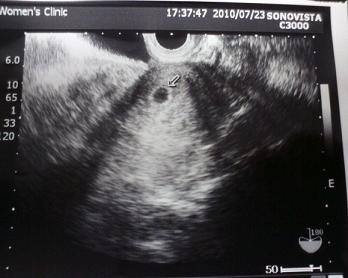

胎のうが確認された時のエコーです。